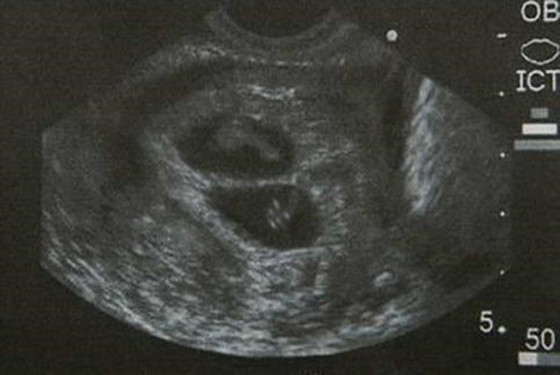

关于怀孕双胞胎三个月肚子有多大,我们可以通过怀孕双胞胎三个月胎儿图去了解,从中我们可以很清晰的看到怀孕三个月胎儿的发育情况。在怀孕三个月的时候,本来安静成长的胎宝宝会变得十分兴奋。准妈妈也会出现各种妊娠反应,有的准妈妈会有强烈的妊娠反应。

三个月的胎儿头部几乎占全长的一半,头发开始出现,五官也逐渐形成,两只眼睛还是相距比较远,下颌和两颊也开始发育。胎儿躯干伸直,尾巴完全消失。上,下肢也已从胎体伸出,并逐渐形成四肢,下肢很短,上肢达到最后的相对长度,指趾分化清楚,并有指甲出现。

四肢开始有活动。胎儿对刺激开始有反应,如眨眼,吸手指,手指脚趾张开等。宝宝在羊水中可以自由活动,有时下肢伸开,做出走的样子,有时又做出蛙泳的样子。但胎儿这时动作轻微,妈妈常感觉不到胎动。但准妈妈您请放心,您腹中的宝宝已经从一个胚胎成长为一个健康活泼的胎儿。